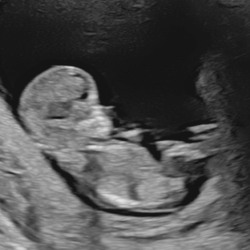

Ik heb al sinds een paar weken last van maagpijn en geregeld zuur. Ik heb ook een zittende job, maar of het echt gerelateerd is geen idee. De baby lag vorige echo in stuit en gynaecoloog gaf aan dat het daar door kwam. Nu moet ik van mijn gynaecoloog tot het einde van de zwangerschap omniprazol nemen. Als ik het zuur krijg, neem ik gaviscon